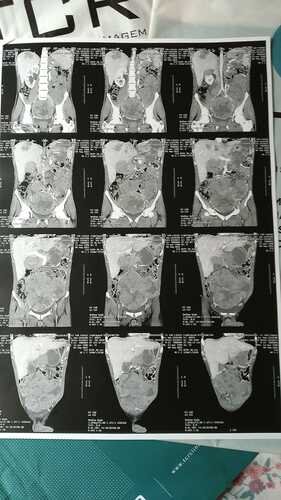

Olá ,Quero aqui ,pedir sua ajuda ! Serei objetivo direto e responsável pelo texto que aqui deixarei. Me chamo Arthur Gonzaga Prata, estou lutando contra um CA ( CARCINOMA CORTEX ADRENAL ) .

Essa Vakinha é para custear alguns exames que pelo SUS é necessário enfrentar uma fila de espera ,tempo este, que não posso esperar, pois meus tumores ,no Peritonio, Pulmões e Fígado, não compreendem essa espera ,me causando muitas dores .Meus pulmões também me alertam ...